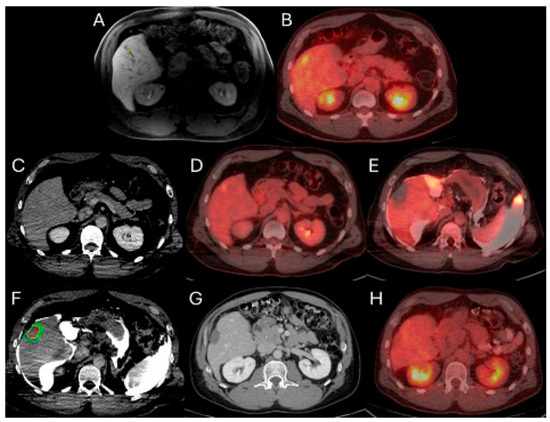

This method offers the significant advantage of allowing continuous visualization of PET-avid tumors through repeated, short breath-hold PET/CT acquisitions in real time, both prior to and during ablation. Real-time PET imaging is capable of detecting most CLMs, including lesions that may not be apparent on non-ceCT scans (Figure 2) [103]. The split-dose PET/CT technique enables precise intraprocedural localization and real-time visualization of the target tumor with electrodes in place, even following hydrodissection or tumor mobilization (Figure 3). This method overcomes the limitations of real-time ultrasound monitoring of the ablation zone, where visibility is often hindered by air produced during ablation. It also provides continuous visualization of the target tumor, enabling precise electrode repositioning to ensure that the ablation zone fully encompasses the tumor. Additionally, tumor viability can be assessed effectively using real-time split-dose FDG-PET [102]. The division of the two FDG doses accounts for the radioactive decay, so that approximately only 10% of the initial dose remains at the final post-ablation scan, which occurs hours after the first injection, thereby minimizing background activity from the original dose. The larger second FDG injection enables precise visualization of the ablation zone and increases sensitivity for detecting hypermetabolic activity from any residual viable tumor after ablation.

Figure 3.

63-year-old female with metastatic colorectal cancer liver dominant disease, previously treated with chemotherapy, hepatectomy, and intraoperative thermal ablations at segment 8, undergoes MWA for new colorectal liver metastasis (CLM) in segment 2. Pre-procedure ceCT ((A,C), black arrowhead) and FDG-PET (B,D) demonstrate the subdiaphragmatic metastasis in close proximity to the coronary sinus and the pericardium. MIM DEV version 3.3.7 semi-automatically generated target tumor and margin contours: using the intra-procedure pre-ablation ceCT, red circle represents the tumor contours, yellow and green circles represent the 5 and 10 mm (mm) margins around the target tumor, respectively (E). Administration of the first dose (4mCi) of FDG according to split-dose protocol provides clear visualization of the FDG-avid tumor (F). Extensive hydrodissection creates a buffer between the pericardium and the edge of the liver (G,H). Short acquisition 1 min breath-hold real-time FDG PET/CT scans confirm accurate placement of the microwave ablation electrode during hydrodissection (I). Second injection of 8mCi FDG confirms absence of residual metabolic activity (J,K). Post-ablation ceCT demonstrates the ablation zone (blue circle) uniformly covering in 3-dimension (3D) the tumor with 5 mm margins, confirming ablation completeness (L).